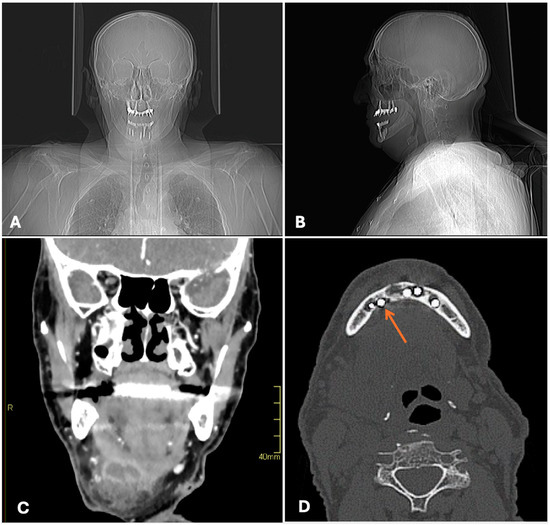

2. Case Description